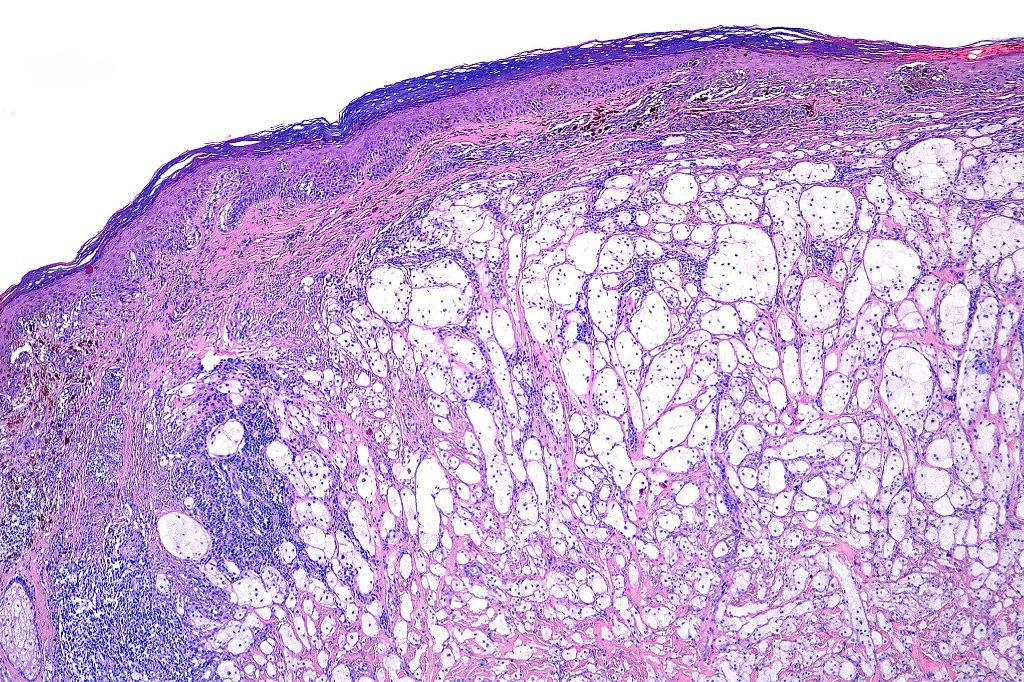

Clinical features

•Back> lower & upper extremities> head & neck> choroid

•Often ulcerated nodules

•Poor prognosis is likely related to large tumor size at presentation